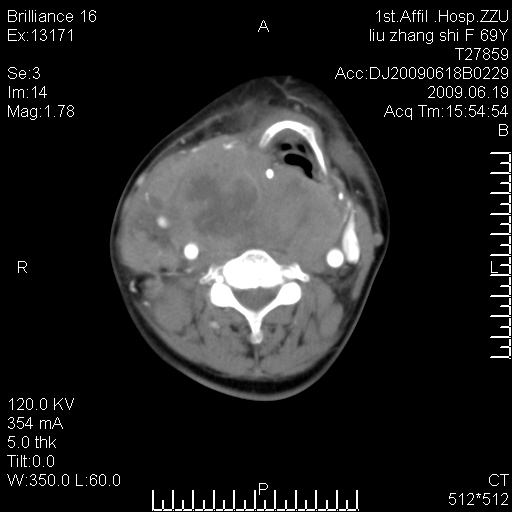

标题: CT26782:女,69岁,颈部占位,3天后公布病理结果。

【病理证实系列】女,69岁,颈部占位,有病理结果,3天后公布。(由于病例时间较久,临床资料不全,请网友见谅)本系列将有几百种常见、少见及罕见病例,均经病理证实。病例资料来自郑州大学第一附属医院。与网友共享,本人有空就发。

甲状腺癌并颈部淋巴结转移。感谢楼主的良苦用心,谢谢。

支持甲状腺癌广泛侵及周围结构并颈部淋巴结转移。

鉴别:淋巴瘤、恶性神经源性病变、恶性纤维组织细胞瘤。

病理结果:颈部非霍奇金淋巴瘤。

右侧甲状腺确实有问题